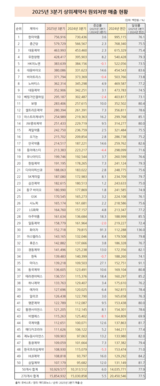

3분기도 원외처방 청신호…화이자 원외처방 91.3% 급증

- 2025-10-15 10:10

- 노영희 기자